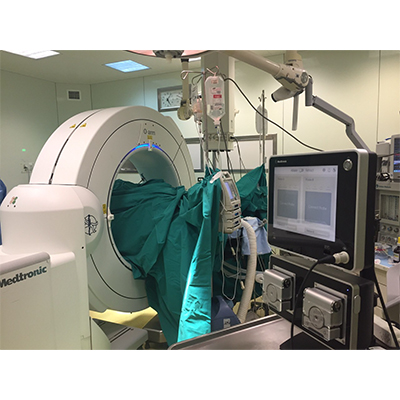

Επιπλέον, με τη χρήση της διεγχειρητικής τρισδιάστατης νευροπλοήγησης (ρομποτική χειρουργική της σπονδυλική στήλης), είναι εφικτή η ταχύτατη, με ακρίβεια και ασφάλεια, εμφύτευση των υλικών οστεοσύνθεσης και η πραγματοποίηση ακόμα και των πιο λεπτών χειρουργικών επεμβάσεων, σε όλες τις περιοχές της σπονδυλικής στήλης, από τον αυχένα έως και το ιερό οστούν. Η διόρθωση της παραμόρφωσης ελέγχεται διεγχειρητικά ενώ ο χειρουργός έχει τη δυνατότητα επιπλέον τροποποιήσεων την ώρα του χειρουργείου, ώστε να πετύχει το καλύτερο δυνατό αποτέλεσμα.

Διεγχειρητική τρισδιάστατη απεικόνιση σε πραγματικό χρόνο (ρομποτική χειρουργική), για την ασφαλή και ακριβή τοποθέτηση των χειρουργικών υλικών σπονδυλοδεσίας (α), αντιμετώπισης όγκου στον αυχένα - σπονδυλοσπλαστική (β, γ), και οστικής μετάστασης στη λεκάνη - θερμική εκτομή του όγκου με ραδιοσυχνότητες(δ)